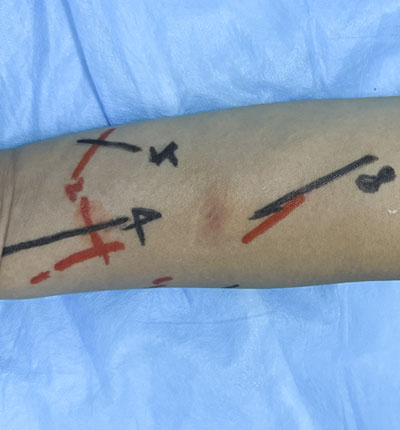

术前超声造影

术前定位